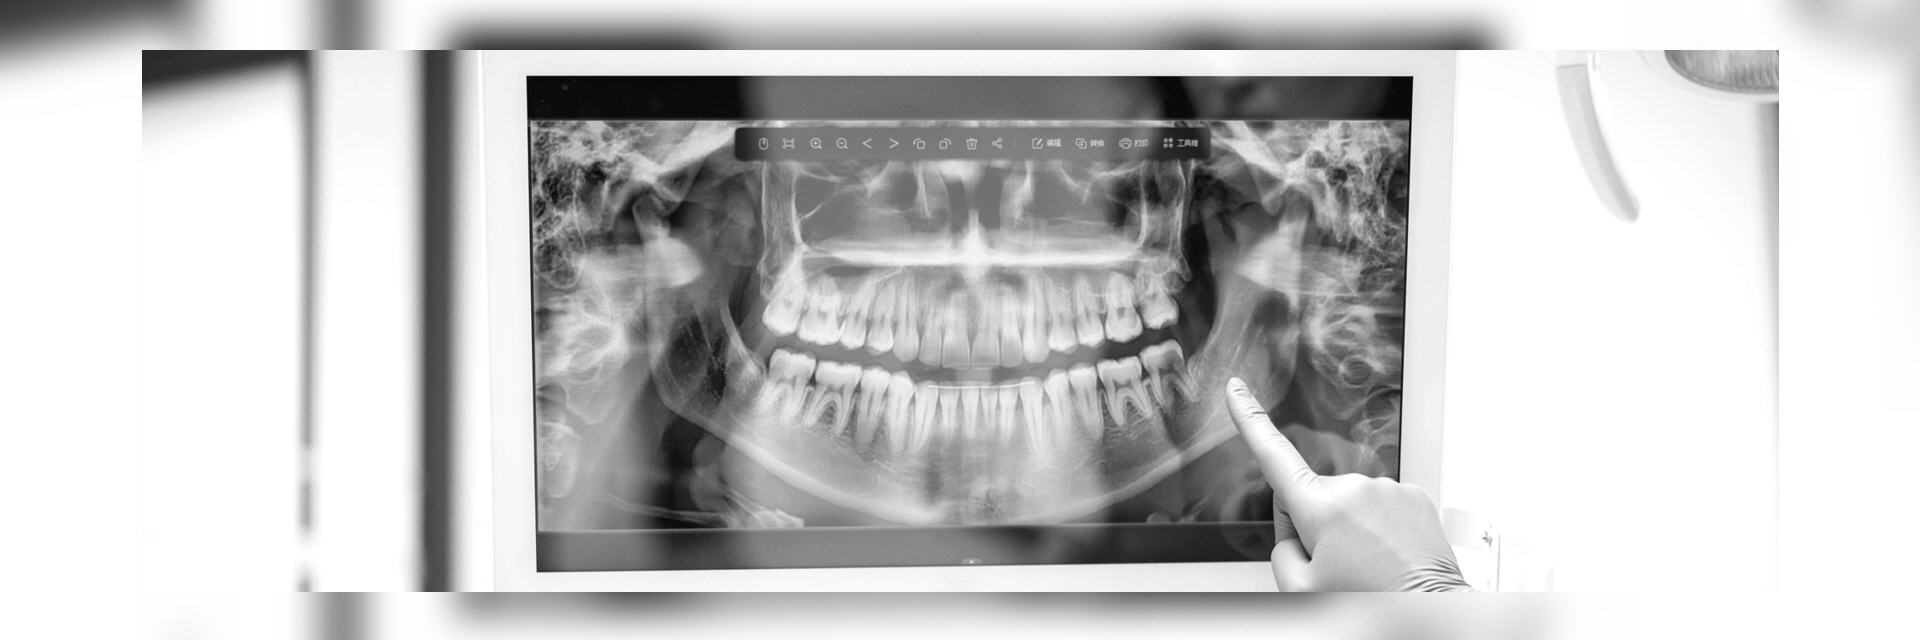

- Orthopantomogramm (OPG) ist eine Panoramaschichtaufnahme des gesamten Ober- und Unterkiefers inkl. der Kiefergelenke in 2-dimensionaler Darstellung. Das Verfahren ist schmerzfrei, strahlenarm und auch bei Würgereiz problemlos durchführbar. Dieses Bild gibt dem Zahnarzt eine Gesamtübersicht und ermöglicht eine Beurteilung der Zahnzwischenräume, der im Knochen befindlichen Wurzeln,

Im digitalen Röntgenbild sehen wir die Vorgeschichte Ihrer Zähne. Also die Spuren des Lebens, die dieses an den Zähnen hinterlassen hat. Dies betrifft Erkrankungen wie die Karies, Spalten unter Kronen oder Füllungen, Wurzelbehandlungen, Entzündungen im Knochen, aber auch Beläge und deren Auswirkungen auf den Zahnhalteapparat also den umgebenden Knochen.